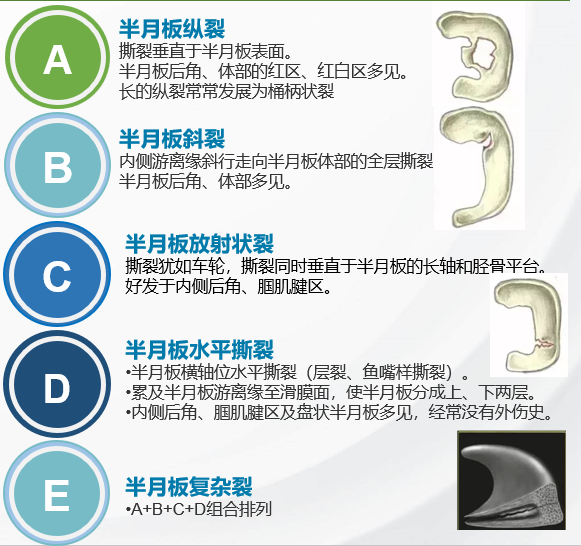

【半月板损伤的分类】

半月板损伤类型的示例

5大类半月板损伤的类型